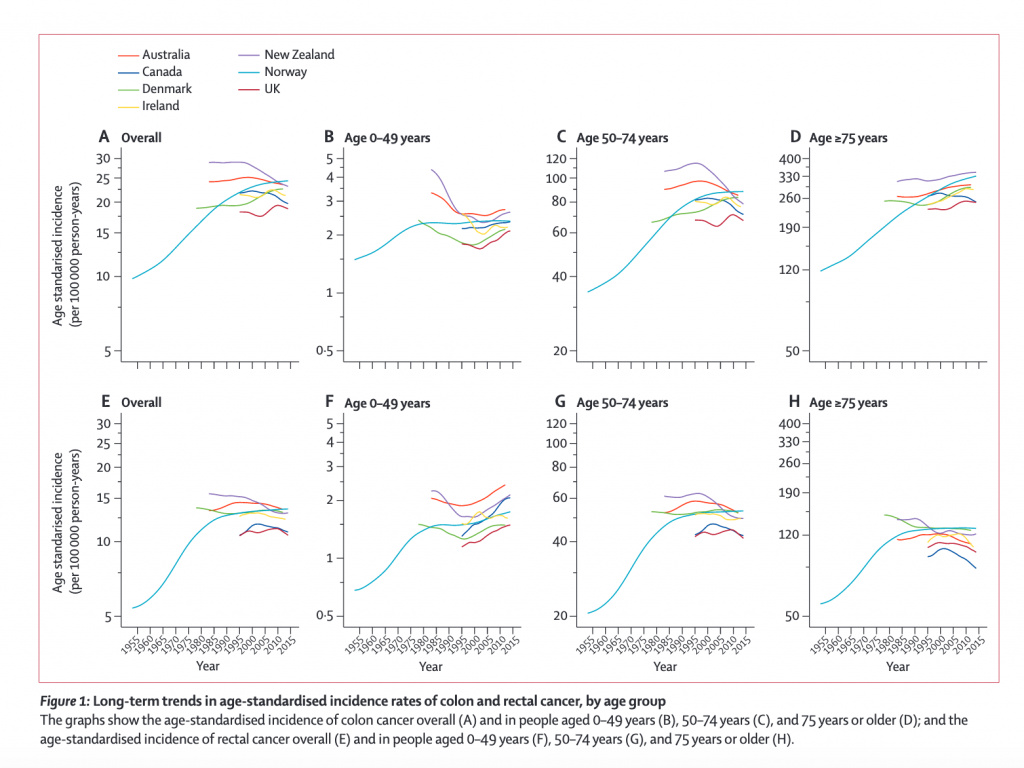

We recently reported an animal study showing that high-fructose corn syrup may be a contributing factor to the rising rates of colon and rectal cancer among young adults. A new observational study from The Lancet Gastroenterology & Hepatology journal looked at long-term data for colon and rectal cancer incidence in 21 population-based registries across Australia (1983-2012), Canada (1995-2014), Denmark (1978-2012), Ireland (1995-2013), New Zealand (1995-2014), Norway (1953-2014), and the UK (1995-2014). It shows that the incidence of colon and rectal cancer in adults younger than 50 years has increased substantially over the latest available 10-year period in certain high-income countries.

In The Lancet data, during the most recent 10-year period up until 2014, the incidence of colon cancer in people aged

Across the same time period, significant decreases in incidence of colon cancer per annum were observed in those aged over 50 in Australia (by 1.6%), Canada (1.9%), and New Zealand (3.4%) and of rectal cancer in Australia (2.4%), Canada (1.2%), and the UK (1.2%).

Trends in the incidence of colon and rectal cancer by age group showed diverging pattern (See Figure 1 and Figure 2 below):

- In people aged 0–49 years, the incidence of colon cancer increased significantly in Denmark (by 3·1%), New Zealand (2·9%), Australia (2·6%), and the UK (1·8%) over the most recent 10-year period (figure 2B), and these increases were more pronounced in women and girls than in men and boys

- In people aged 0–49 years, an increase in incidence was noted particularly for tumors occurring in the distal (left-side) colon (appendix pp 5, 11). In people aged 0–49 years, the incidence of rectal cancer increased significantly in Canada (by 3·4%), Australia (2·6%), and the UK (1·4%; figure 2F).

- Analyses by age subgroup showed that, among people aged 20–29 years, there were significant and large increases in the incidence of colon cancer in Denmark and Australia, and a significant decrease in incidence this age group in Canada (figure 3; appendix p 6).

- There was also a significant increase in the incidence of rectal cancer among people aged 20–29 years in Denmark. The increasing incidence of colon cancer was driven largely by increases in the incidence of distal colon cancer both overall (appendix pp 5–6, 11) and in people aged 20–29 years (appendix p 7).

The authors of the study suggest that the decrease in incidence of colorectal cancer in people over 50 years old in most of the countries studied could be attributed to the introduction of routine screening programmes for premalignant polyps. In Australia, Canada, and the UK, where age-based screening began in 2006, overall decreases in incidence were more pronounced. In those countries where screening programmes began later, such as in Ireland (2012), Denmark (2014), Norway (2012, pilot programme only), and New Zealand (2017), overall rates have remained roughly stable.